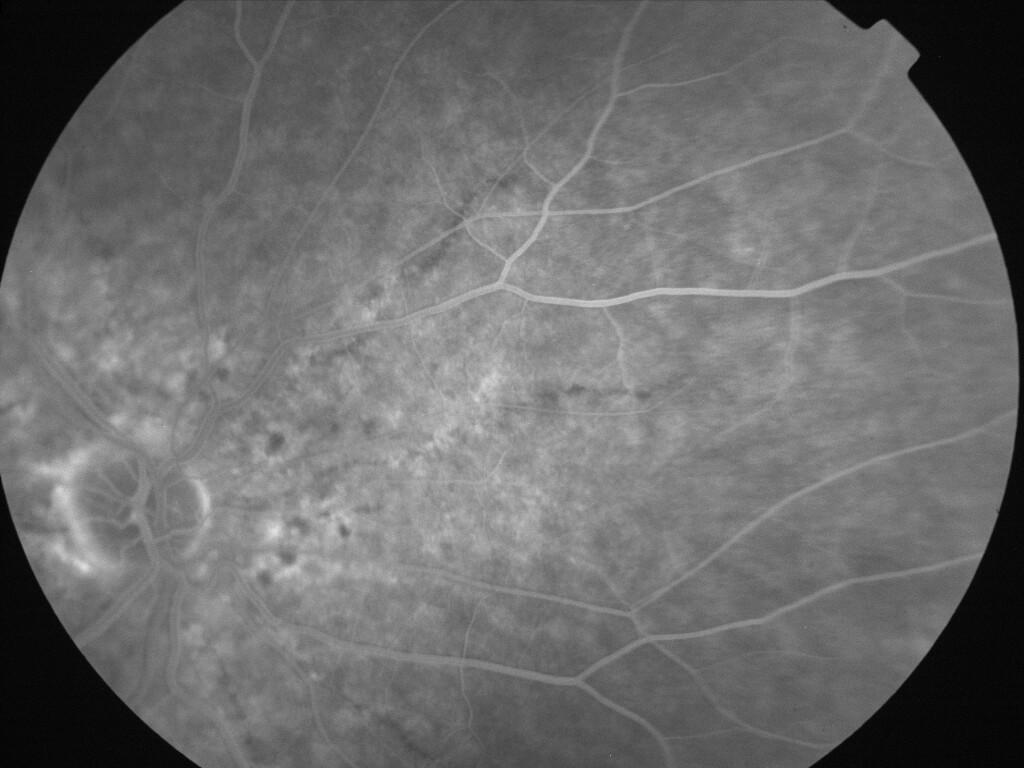

IMG0038.jpg